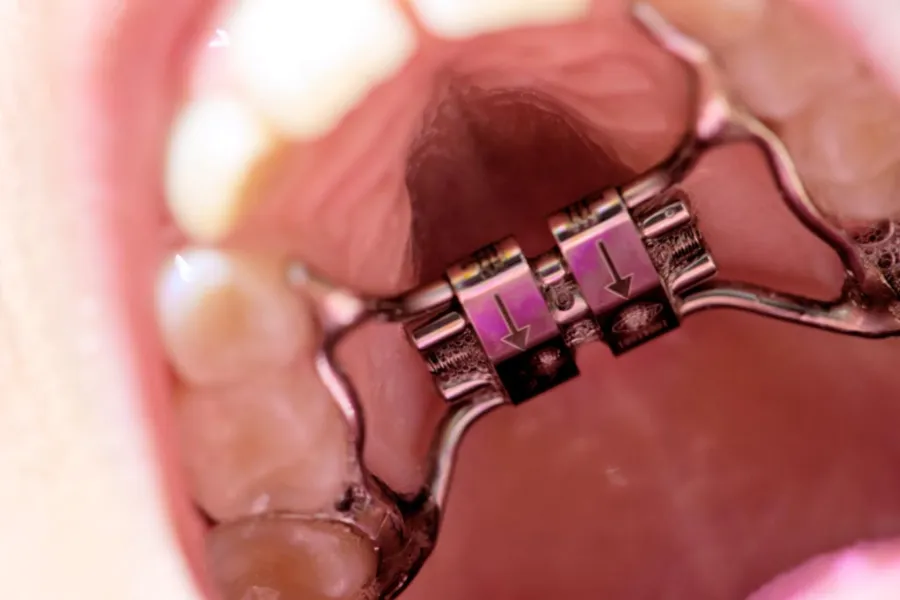

La ortodoncia interceptiva es una especialidad clave dentro de la odontopediatría, diseñada para corregir problemas dentales y de crecimiento maxilar en niños desde edades tempranas. Su principal ventaja es que actúa antes de que los problemas se agraven, evitando tratamientos más invasivos y costosos en el futuro.

El precio de la ortodoncia interceptiva en Perú varía según el tipo de aparato, la complejidad del caso y la clínica donde se realice el tratamiento.